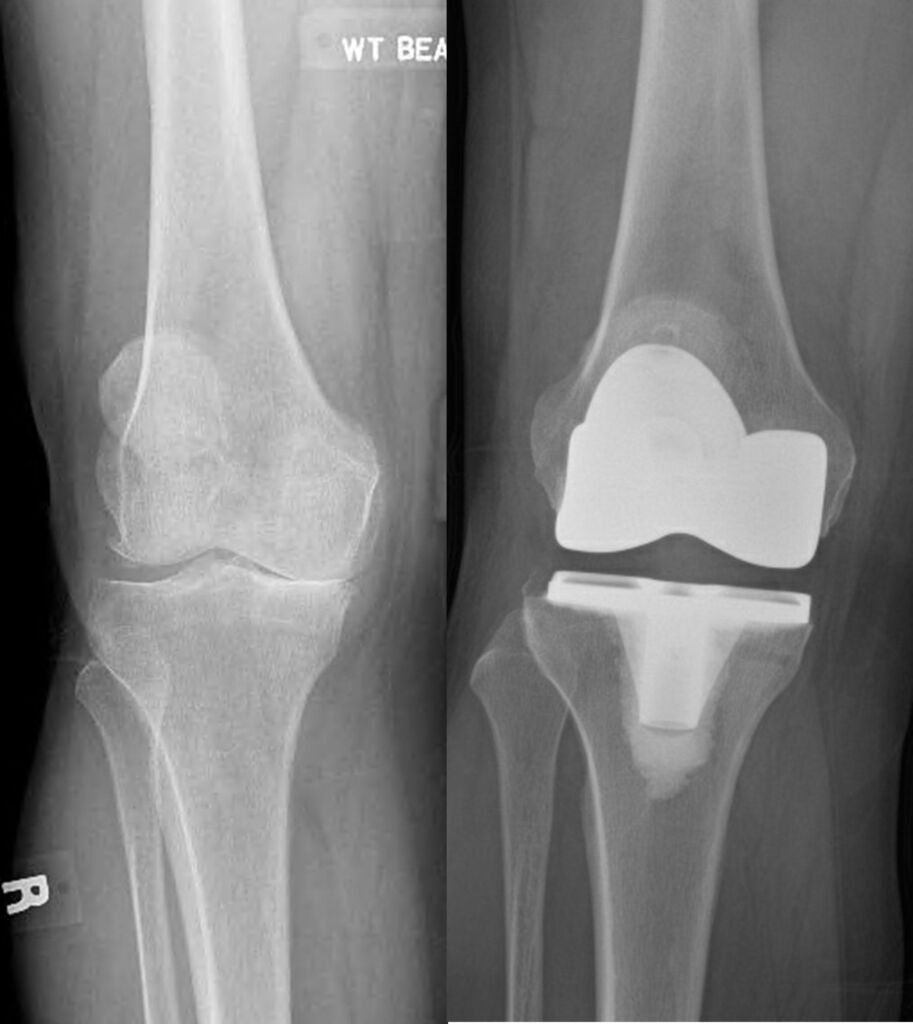

Advanced knee arthritis – left image,

Total knee replacement – right image